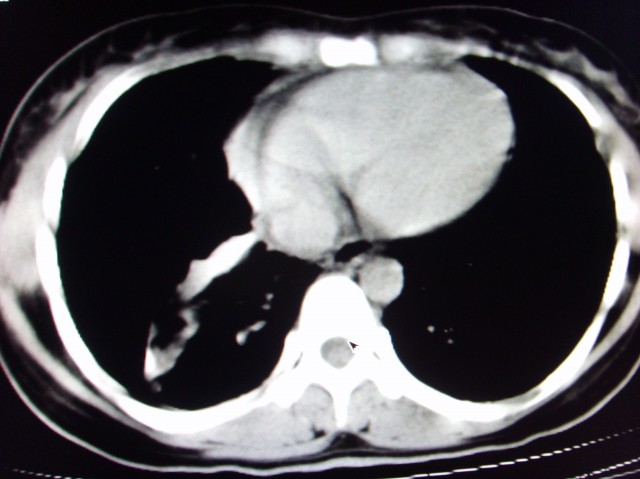

标题: CT7125:中央性肺Ca.

典型 中央型ca伴双肺、淋巴结转移

右下中心型肺癌伴双肺转移、纵隔淋巴结转移,癌性淋巴管炎可能性大

支持楼主的中央型肺癌,肺内,纵隔内淋巴结转移

支持楼主诊断:中央型肺癌,肺内,纵隔内淋巴结转移。

典型--右下中心型肺癌伴双肺转移、纵隔淋巴结转移,癌性淋巴管炎可能性大

典型的中央型ca,肿快和肺门分界不清,肿快边界模糊,呈毛刺状。伴淋巴结转移。